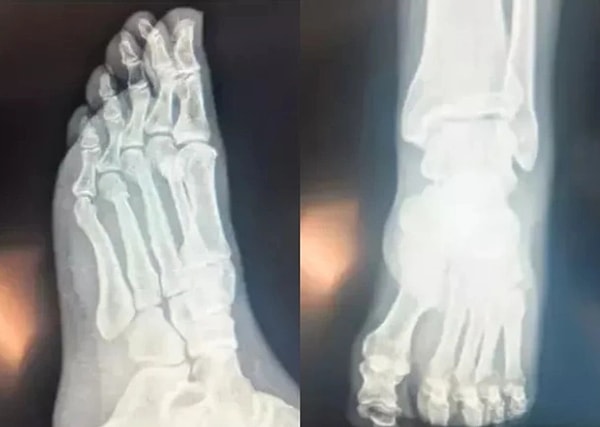

'Ayağından Vuruldu' İddiaları Sonrası Özgür Özel'den Röntgen Filmi Paylaşımı!

CHP Genel Başkanı Özgür Özel, 'ayağından vuruldu' iddialarının önüne geçmek amacıyla ayak röntgen filmlerini paylaştı.

Sözcü Gazetesi'nden Saygı Öztürk'e konuşan Özgür Özel, FETÖ'cü hesaplardan servis edildiğini iddia ettiği paylaşımların önüne geçmek için ayak röntgen filmlerini paylaştı.

Özgür Özel şunları söyledi: "Herkesin başına gelebilecek, geçirdiğim bir ev kazası üzerinden, hepimizin kimler olduğunu iyi bildiği bir grup, sosyal medyadan akıl ve ahlak dışı bir kampanya başlattı. Tarihsel husumetimiz olan FETÖ’cü hesapların yaydığı bir yalan."

'Bu gündemlere teslim olacak değiliz. Bu konuda açıklama yapmayı bile aslında zül sayıyorum. Biz işimize bakıyoruz. Bizim gündemimizde memleketin sorunları ve bu sorunlara üreteceğimiz çözümler var.'